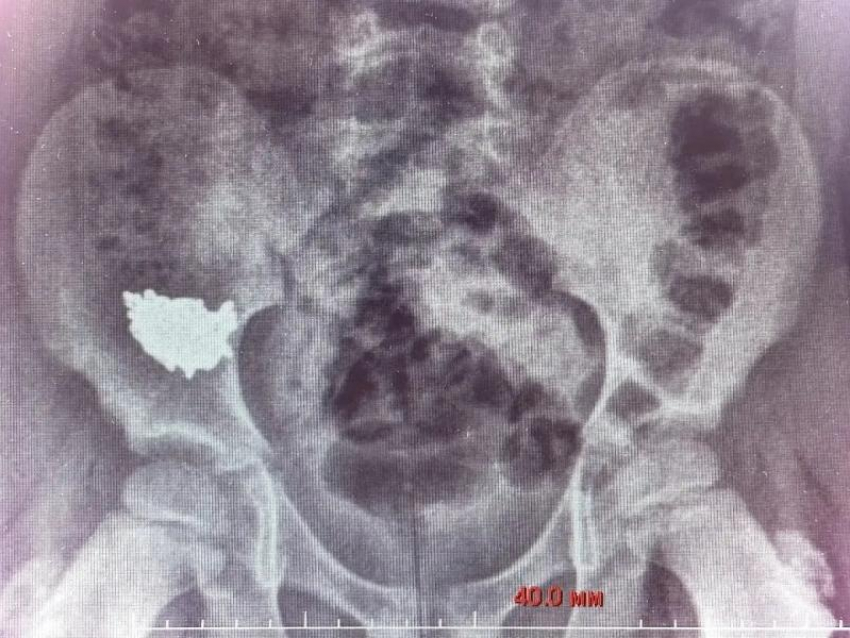

Как рассказали в региональном Минздраве, медики после сделанного рентгена увидели, что инородное тело находится в правой подвздошной области (часть тела человека, расположенная внизу живота). Пациента госпитализировали.

«Снимки на третьи и четвёртые сутки после обращения показали, что цепочка не двигается по ЖКТ, находится в правой подвздошной области», – резюмировал детский хирург Владимир Кораблёв.